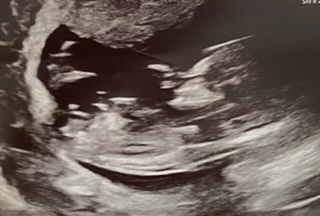

Hi all I’m sorry I think I just posted this in the wrong place, just looking for some guesses on my 13+1 scan we’re pretty sure of what we think we saw on the screen. TIA x

I am suspecting your partner saw that sticky outy thing and assumes it is a penis, but see how straight it is?? My guess is girl. Now, it is still a bit early, and that can and in some cases DOES rise and then babies that looked like girls will be revealed to actually be boys, but as it sits now that looks like a girl to me. :heart: huge congrats!

Hey just to let you know we had our gender scan, he is all boy and proud of it x